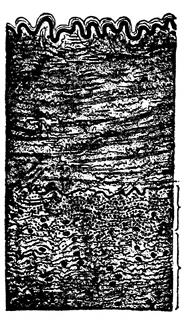

Fig. 5—Cross section of

bone. (Sharpey)

If a cross section is made of any

long bone, such as the humerus,

and this section placed under the

low power of the microscope, the

Haversian canal system can be

discerned. The Haversian canal

system consists of the numerous

small openings or canals through

which the blood vessels ramify in

distributing the nourishment to

the bone. Around each individual

canal are seen smaller spaces arranged

in a circle. These are known

as the lacunae (small lakes). Going from the lacunae

are smaller canals which take on the name canaliculae,

and joining all the lacunae together, making the appearance

of concentric circles, we have the lamellae. The

outside covering of the bone is called the periosteum and

the inside covering is called the endosteum. Most of

the long bones and many of the smaller bones are supplied

by a nutrient artery, which enters the bone near

its center, enters the bone marrow, and divides into

two branches, one going up and the other down in the

marrow. The blood is then distributed through the Haversian

canal system. Veins emerge from the long bones

in three places: 1. One or two large veins accompany

[51]

the nutrient artery. 2. Numerous veins emerge from

the articular extremities. 3. Many small veins arise

in and emerge from the compact substance.